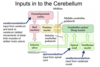

List whether the superior, middle, and inferior cerebellum peduncles have mainly afferent or efferent fibres in them

Superior: mainly efferent (sending the message up high to the cortex)

Middle (Largest): Receiving information, so afferent

Inferior: Receiving information, so afferent